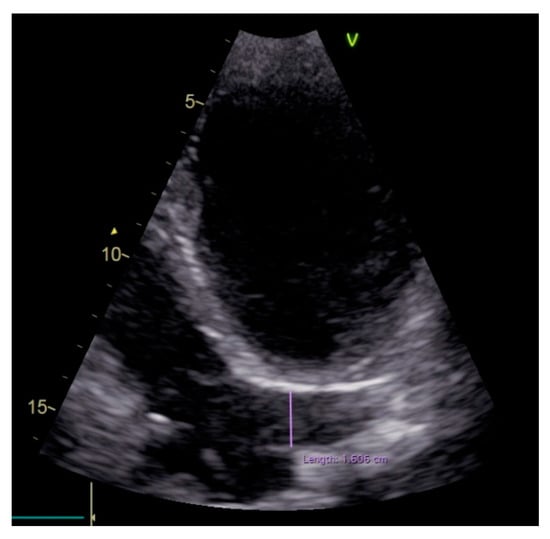

2. Case Report